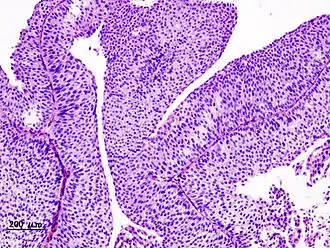

Image histopathologique d'un carcinome urothélial de la vessie. Biopsie transurétrale. Coloration H&E.